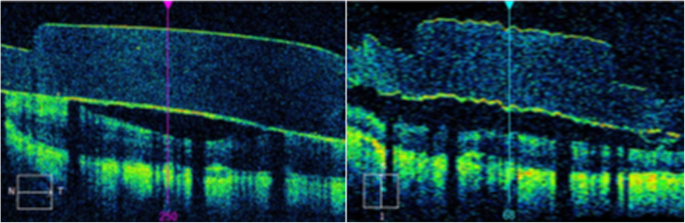

A Cirrus HD-OCT Machine was utilized by the PAS study to capture images during each patient visit. Parameters for capture at each visit included a 6 mm × 6 mm macular cube image (acquiring 512 nasotemporal scans × 128 superoinferior scans) which were utilized for study purposes. Images were located using unique patient identifiers and analyzed using Zeiss OCT analytical software. Eligible scans included a majority of the 60 electrodes and a surrounding portion of retina, the ability to visualize or estimate the precise location of each electrode, and a signal strength of at least 5 out of 10 (determined by the Zeiss software). While in the macular cube view of the software, the perpendicular nasotemporal and superoinferior raster lines were placed directly over the center of each visualized electrodes (Fig. 1). On the associated horizontal and vertical tomograms, the built-in caliper measurement tool was used to measure the vertical distance (in μm) between the electrode array and retina (Fig. 2). These measurements were taken for each patient at M3, M6 and Y1. The electrodes were designated a label (A-F, 1–10) to ensure consistency of measurements at each visit. Out of 1200 electrodes, 1124 (93.7%) were able to be measured.

OCT macular cube horizontal and vertical tomograms. After targeting a specific electrode with the raster lines, the software’s caliper measurement tool was used to measure the distance along the raster lines between the electrode array and the surface of the retina on the associated horizontal and vertical tomograms